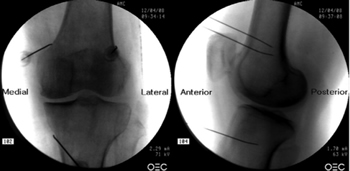

Figure 2